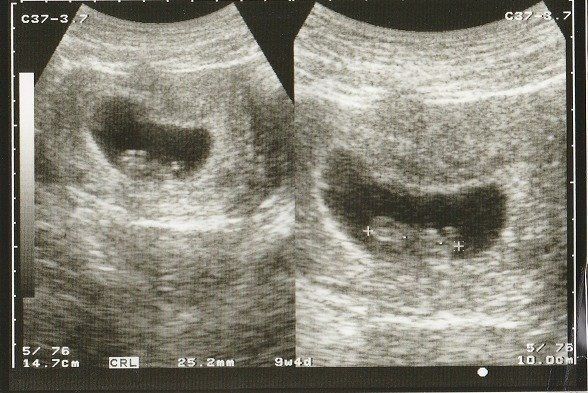

妊娠9週目のエコー写真 何となく人の形?

落花生のように真ん中がくびれた胎児の形が見えるようになってきました。